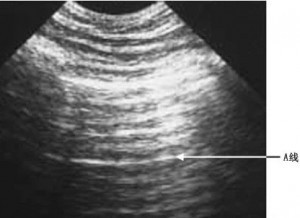

气胸的超声诊断标准为: 1. 肺滑动征缺失;2. 肺点征;3. 彗尾征缺失;4. 平流层征。同时以 X 线为确诊标准,研究超声的诊断准确性,其次还比较了超声和 X 线摄片所需要的时间。

42 名婴儿确诊气胸,符合准入标准。超声诊断气胸为 26 人 (61.9%),其余 16 人出现急性失代偿。肺部超声的敏感性为 100%,特异性为 100%,阳性率为 100%,阴性率为 100%,临床诊断的敏感性为 84%,特异性为 56%,阳性率为 76%,阴性率为 69%。肺滑动征和彗尾征均缺失的敏感型为 100%,肺点征的特异性为 100%。肺部超声平均时间为 5.3±5.6 分,X 线平均时间为 19±11.7 分。

研究表明,超声诊断比临床诊断具有更好的准确性,肺部超声能很好的用于诊断重症气胸急性失代偿的患儿,有经验的医师能使检查时间显著缩短,避免诊断和治疗延误,没有辐射是超声在气胸诊断中推广的主要优势。